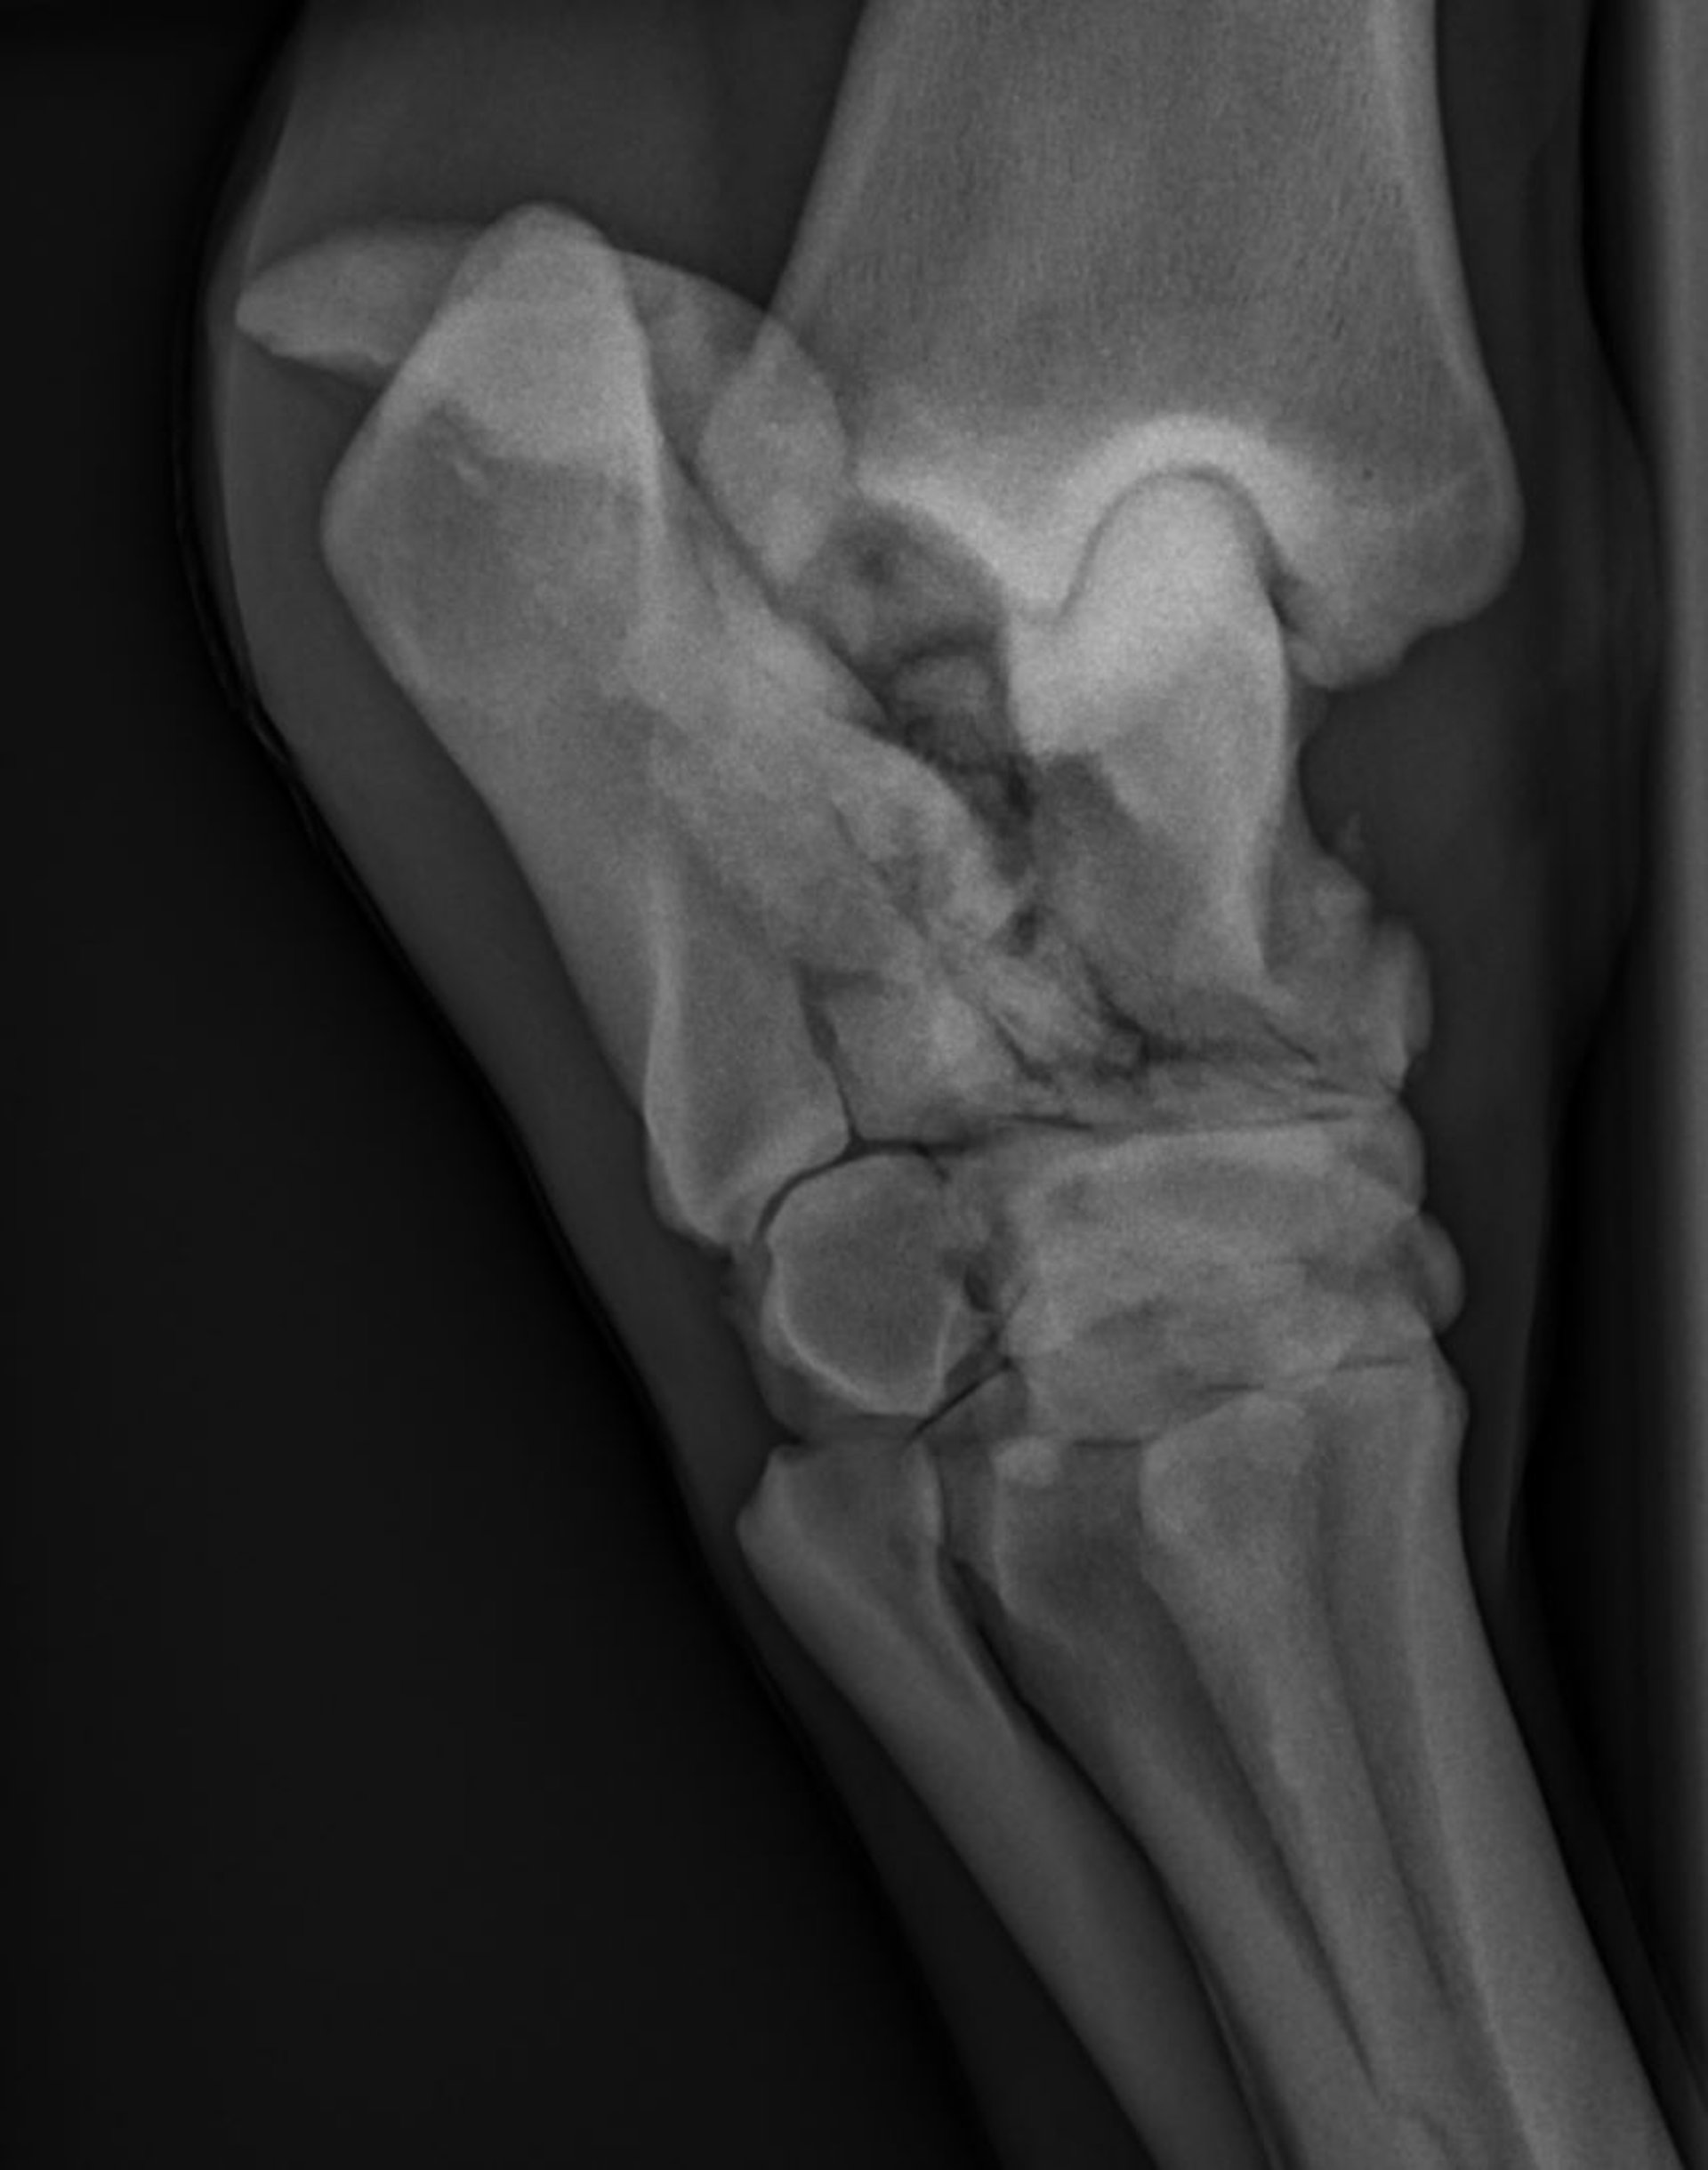

Dorsolateral-plantaromedial radiograph of a horse, showing a severely comminuted fracture of the talus and calcaneus.

Courtesy of Dr. Hilary Rice.